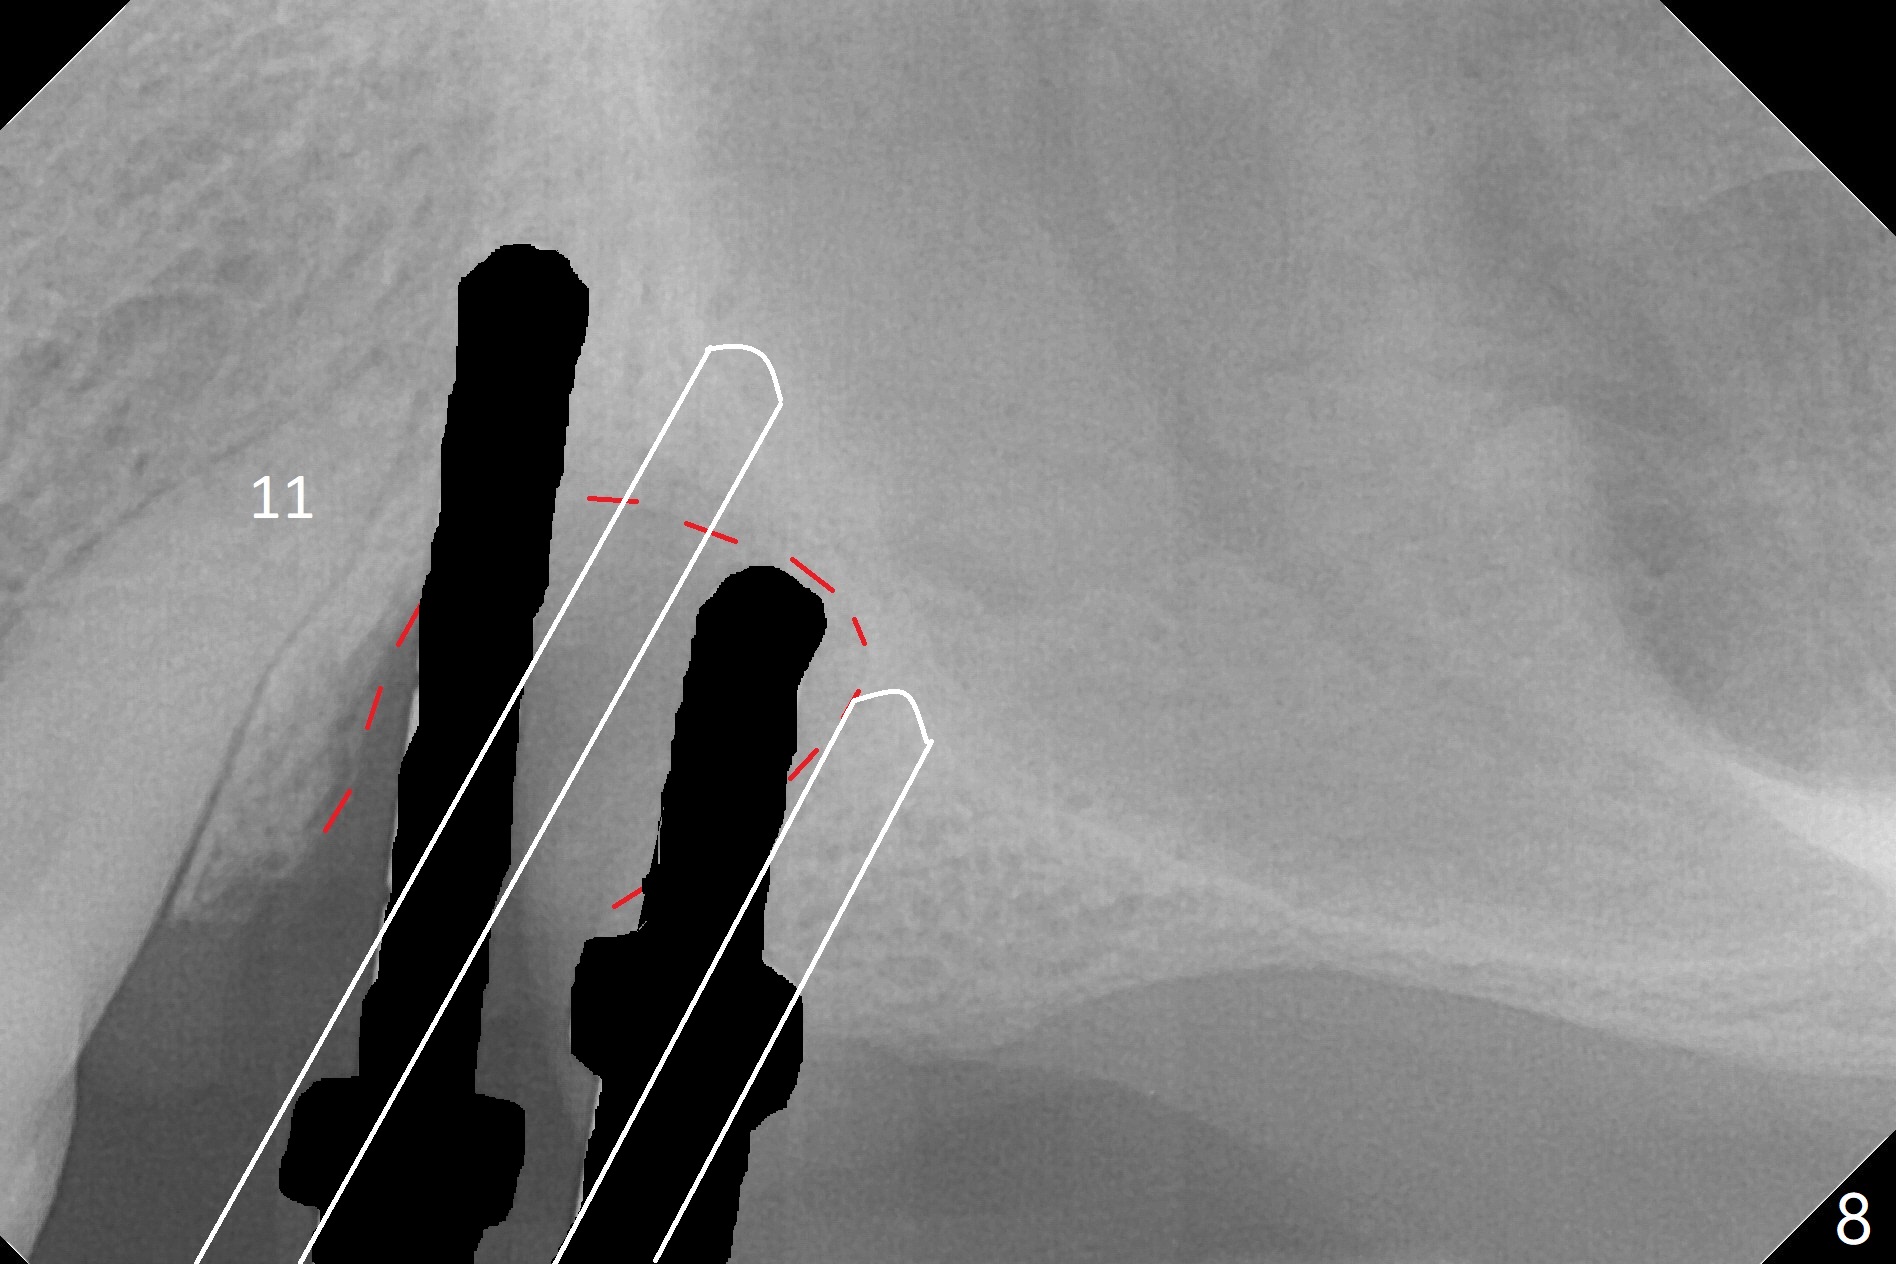

The buccal gingiva at #12 with vertical root fracture looks unhealthy (Fig.1). Osteotomy at #13 is initiated prior to #12 extraction. In fact the osteotomy happens in the extensive defect associated with #12 (Fig.2 red dashed line). To obtain primary stability, the osteotomy at #12 needs to be long, while that at #13 needs two-pointed fixation (Fig.3 *). After adjustment of trajectory at #12 and increase in diameter of the osteotomy at #13 (Fig.4), a 3.8x15 and 3.8x10 mm implants are placed (Fig.5). Following adjustment of implant depth (Fig.6), the implant at #12 becomes loose, while that at #13 tightens. With placement of abutments, an immediate splinted provisional is locked in place to stabilize the loose implant at #12 (Fig.7). The patient complains of cold sensitivity in the upper left quadrant, possibly related to the fact that the implant at #12 is close to the apex of the tooth #11. The position and trajectory of the initial osteotomies should be changed as shown in Fig.8 (white lines, as compared to Fig.2). There is no sensitivity 1 month postop. Impression is taken 4 months postop (Fig.9) after #13 mesiobuccal margin prep. The implants were placed too close to each other. The abutment screw at #13 is retightened 8 months post cementation. There appears no bone loss 9 months post cementation (Fig.10), while the tooth #11 has periapical infection with DL caries 1 year 7 months post cementation (Fig.11).